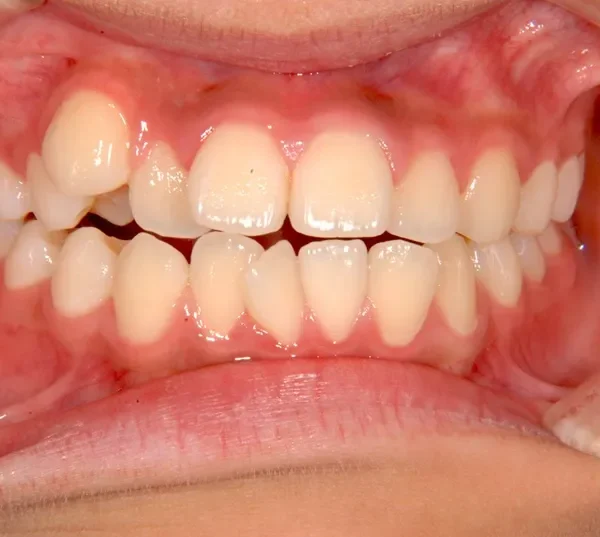

治療終了後

前歯で噛めない(開咬/オープンバイト)

歯ががたがたで、噛み合わせもずれています。

上下前から見える装置をつけ治療しました。歯は抜いてないです。

治療回数57回、6年9ヶ月の治療期間で矯正治療を終了しました。

主訴が改善され、ご満足頂きました。